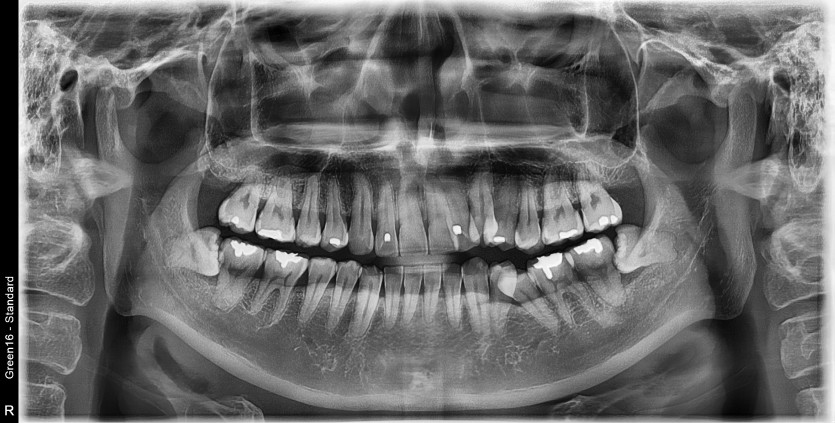

#38 사랑니 발치

구강 외과 전문의가 당일 발치했습니다.